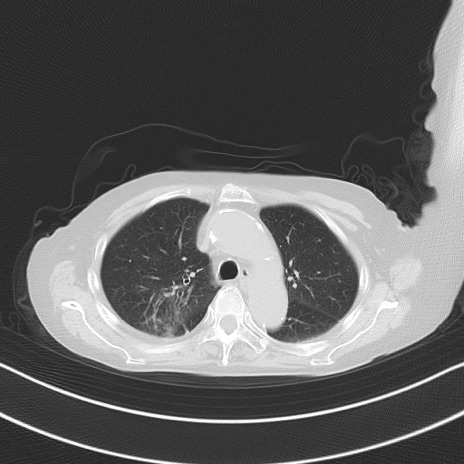

横断像

他院CT